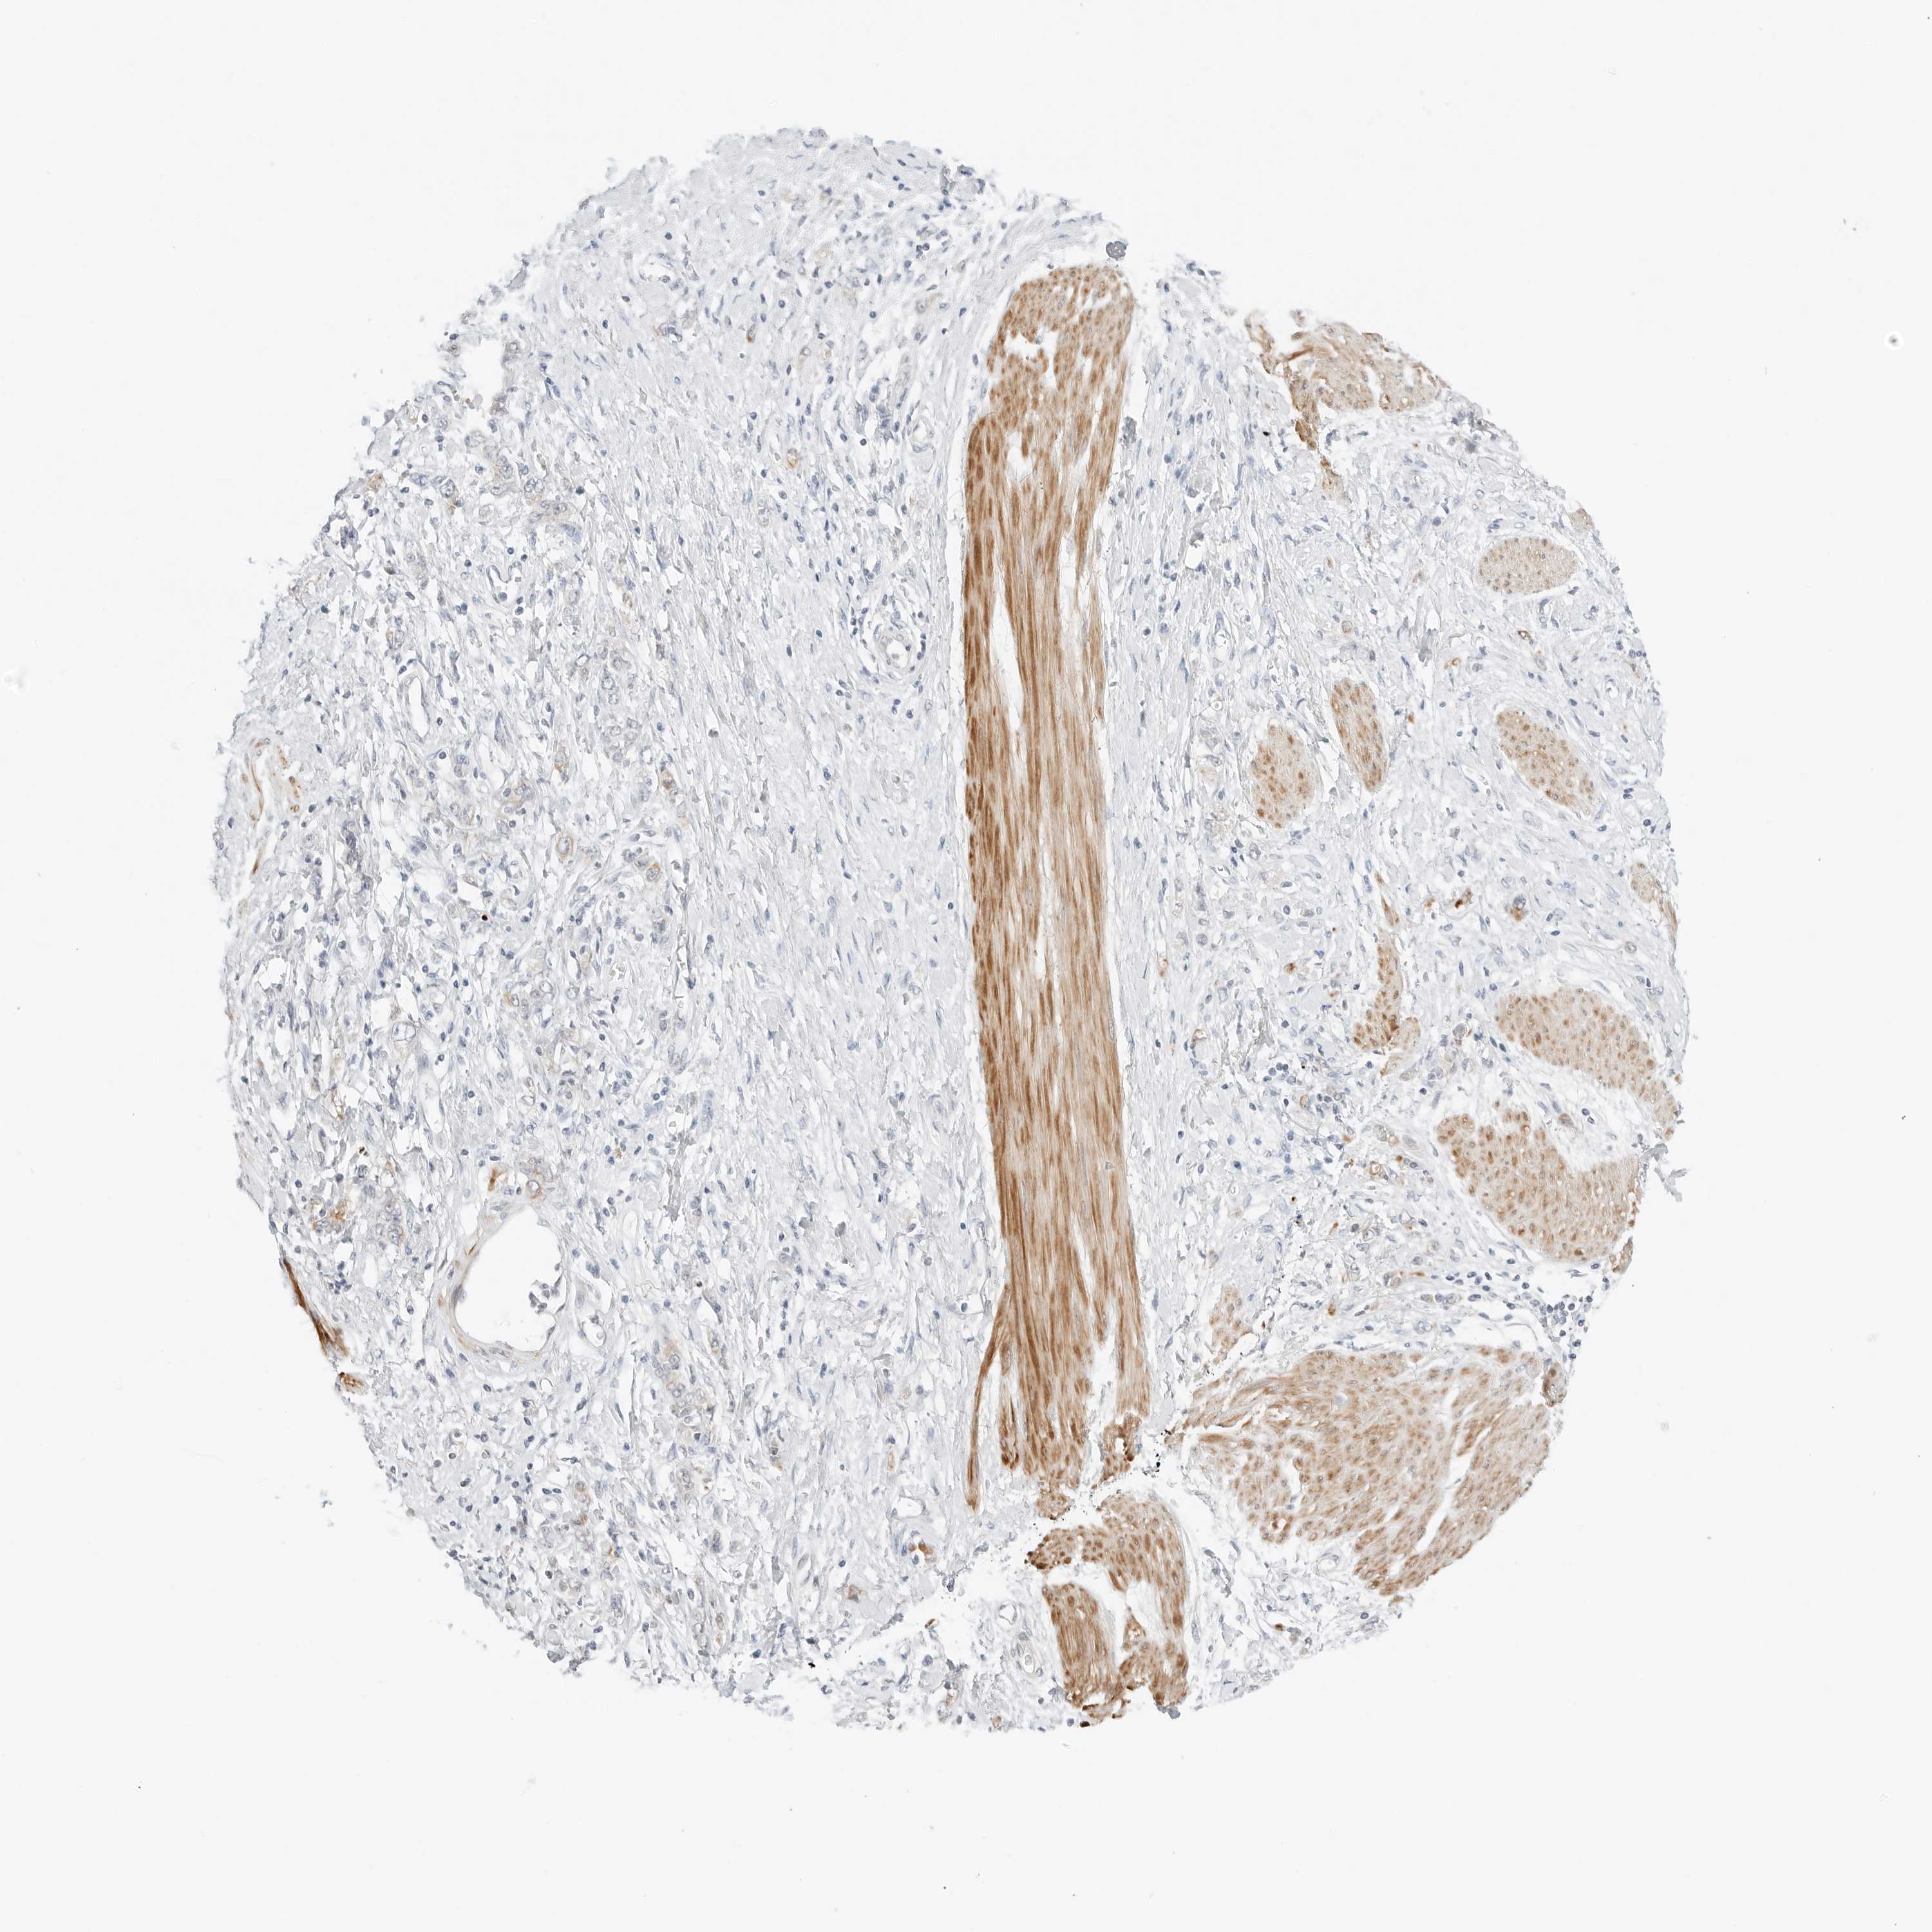

STOMACH CANCER - Protein expressioni

A mouse-over function shows sample information and annotation data. Click on an image to view it in a full screen mode. Samples can be filtered based on level of antibody staining by selecting one or several of the following categories: high, medium, low and not detected. The assay and annotation is described here.

Antibody stainingi

Antibody staining in the annotated cell types in the current human tissue is reported as not detected, low, medium, or high, based on conventional immunohistochemistry profiling in selected tissues. This score is based on the combination of the staining intensity and fraction of stained cells.

Each image is clickable and will lead to virtual microscopy that enables deeper exploration of all samples and also displays staining intensity scores, fraction scores and subcellular localization as well as patient and tissue information for each sample.

Antibody HPA028602

Antibody HPA028686

Adenocarcinoma, NOS